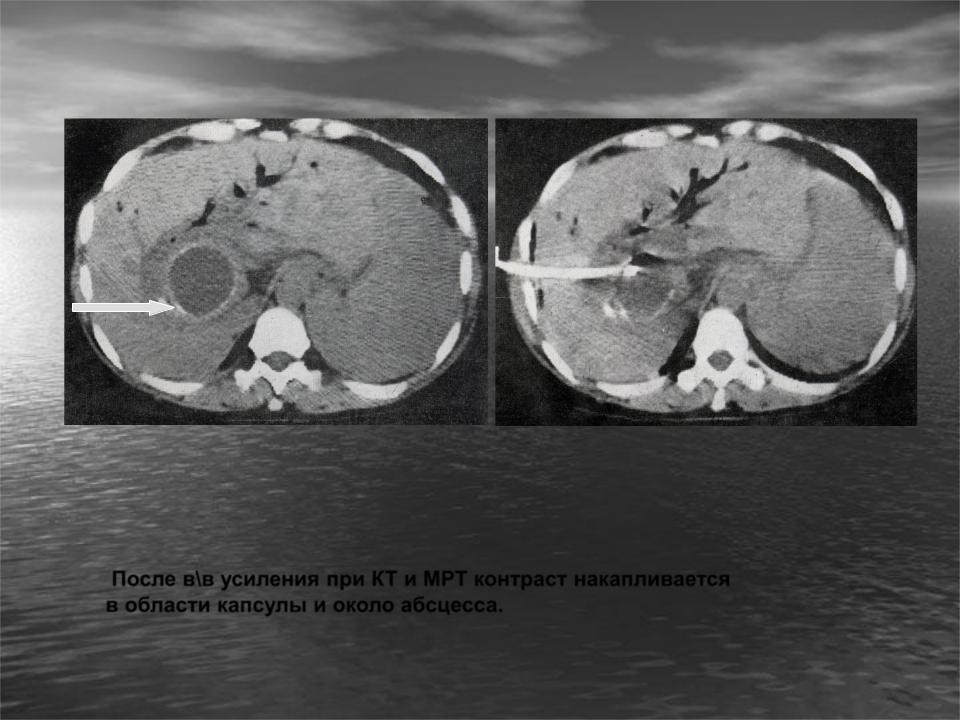

Методы динамического контрастирования печени на МРТ

Раздел: Снимки-подсказки